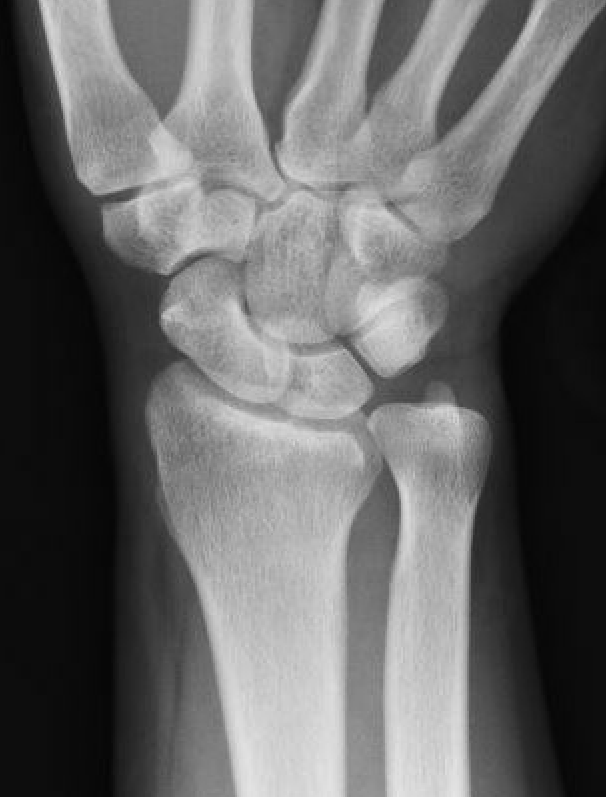

| Stage IIIB | Stage IV |

|---|---|

|

Collapse / fragmentation Scaphoid flexed / Capitate migrates proximally |

Pancarpal osteoarthritis |

![]() |